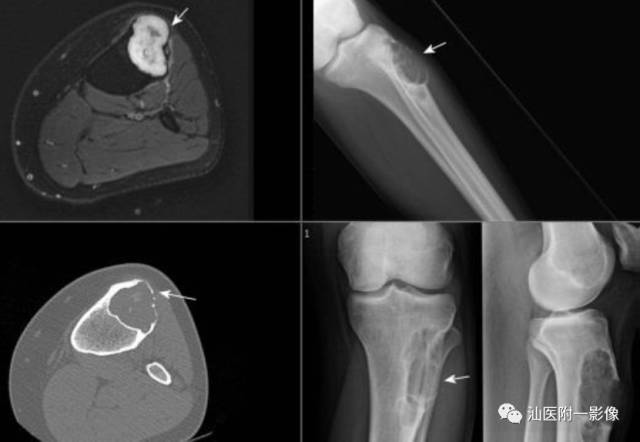

1.非典型软骨性肿瘤/软骨肉瘤I级

3.软骨黏液样纤维瘤

•一种少见的以分叶状生长的黏液样和软骨样分化的骨肿瘤,起源于形成软骨的结缔组织,并具有黏液样、软骨样及纤维样特征。

•10-30岁多见,占71%,好发长骨干骺端和骨端

影像学表现(缺乏特异性)